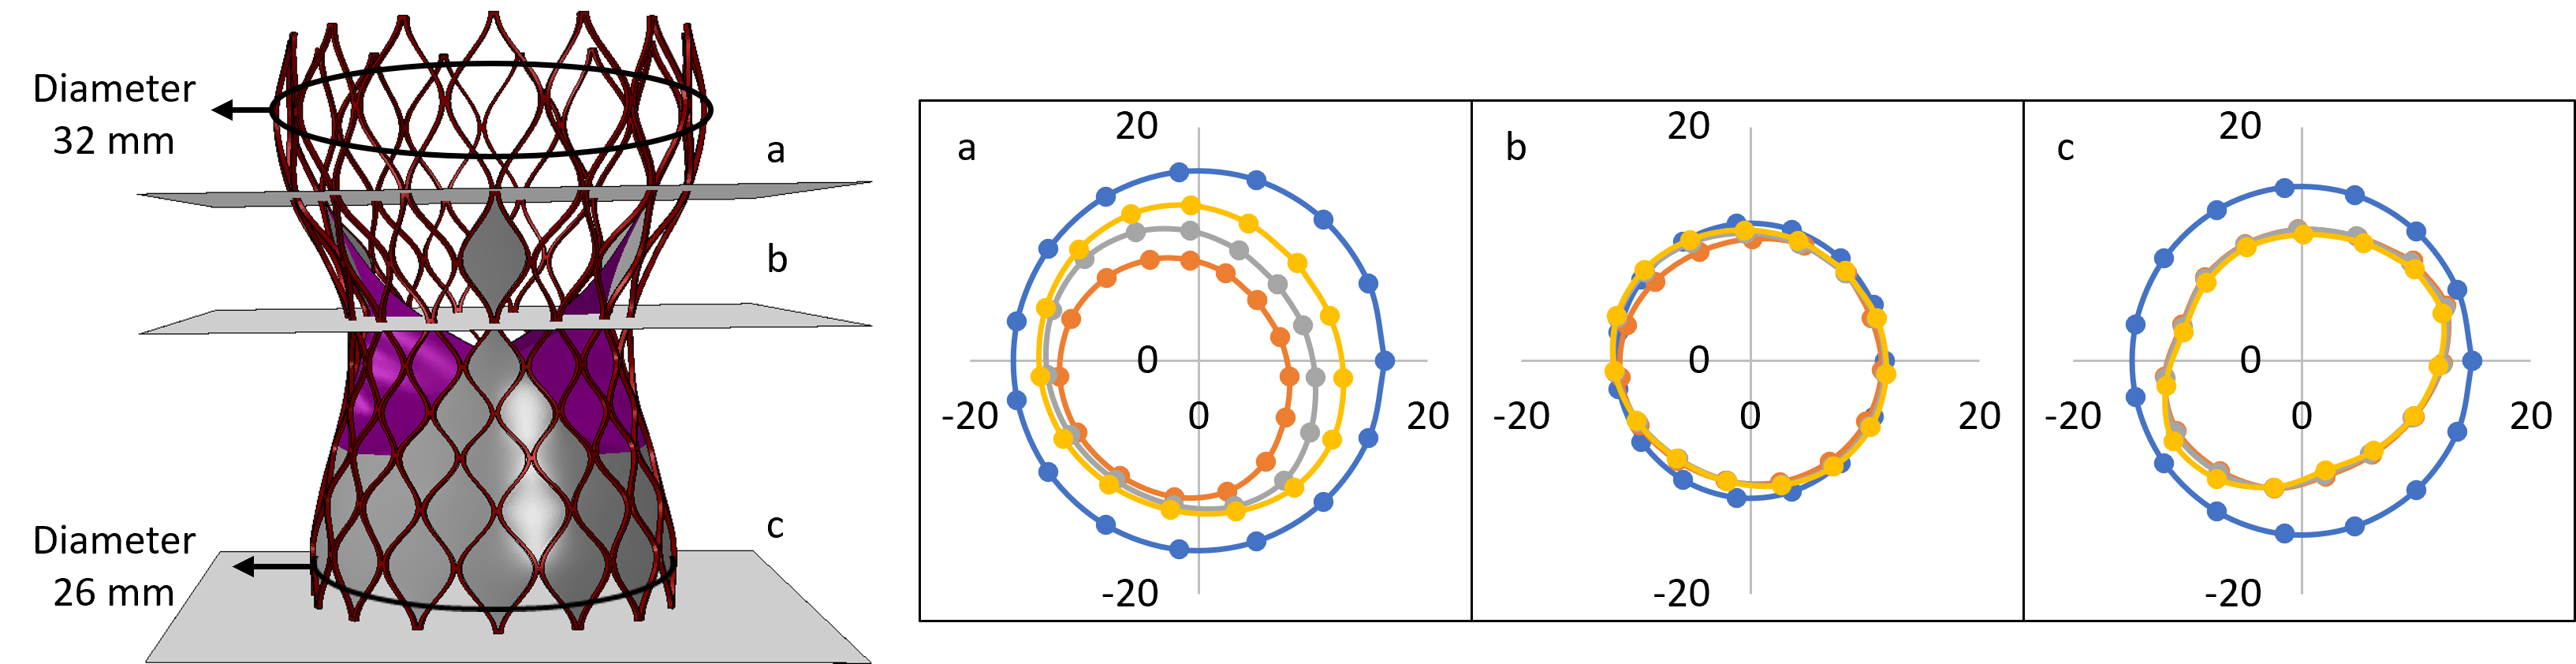

- In this study, we presented a comprehensive framework to analyze structural analysis of TAVR deployment, hemodynamic analysis via FSI simulation coupled with thrombogenic risk assessment via Lagrangian particle tracking.

Patient model reconstruction and TAVR deployment

Patient model reconstruction and TAVR deployment

Structural analysis of device eccentricity

Hemodynamic analysis

- A smaller STJ size impairs adequate expansion of the TAVR stent, which may lead to suboptimal hemodynamic performance.

- Larger STJ size marginally enhances the hemodynamic performance but increases the risk of TAVR leaflet thrombosis. Such analysis can aid pre-procedural planning and minimize the risk of TAVR leaflet thrombosis.